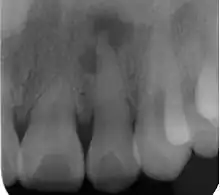

Radiograph (X-ray) showing microdontia. Note also periapical lesion on the maxillary left lateral incisor.

Microdontia is a condition in which one or more teeth appear smaller than normal. In the generalized form, all teeth are involved. In the localized form, only a few teeth are involved. The most common teeth affected are the upper lateral incisors and third molars.